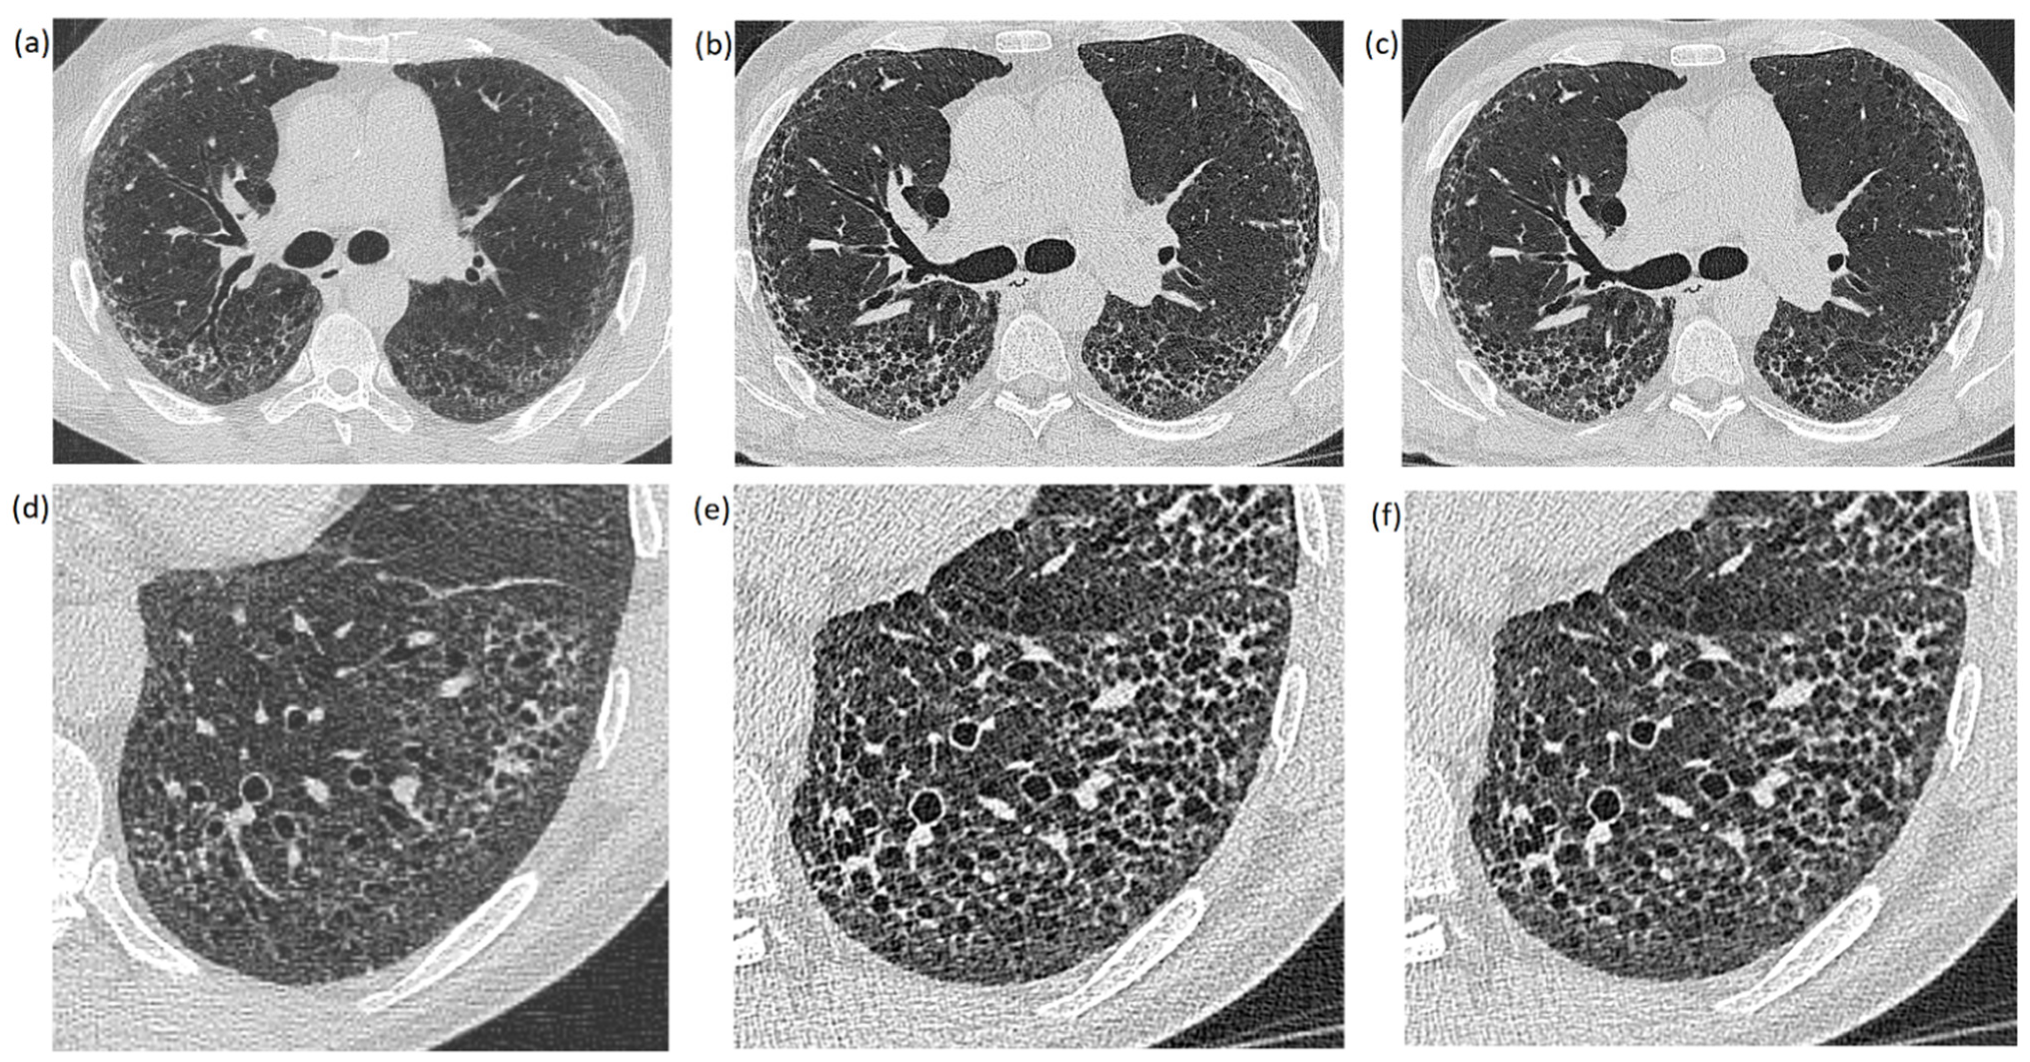

The reconstructed images were analyzed retrospectively using a standard PACS system (IMPAX 6.7, Agfa Healthcare, Mortsel, Belgium). All images were reconstructed in axial view with the same slice thickness (1 mm) on both CT scanners. The PCCT images were reconstructed with quantum iterative reconstruction (QIR, level Q2) and without QIR. The S64 images were reconstructed without iterative reconstruction algorithms. Consequently, 6 images of each patient were compared at the same anatomical position: 3 images pictured the whole lung (Figure 1a–c), while the other 3 images showed an enlarged image section displaying a specific finding (lesion) (Figure 1d–f). The images of the whole lung were leveled at the carina while the leveling of image sections varied between patients in accordance to the anatomic position of the displayed lung lesion. Window settings were constant in all images (center: −500 and width: 1700), which represents the standard window settings used at our institution.

Figure 1.

Images of the whole lung (a–c) and enlarged image sections (d–f) of the same patient: (a,d) were created with the EID-CT scanner; (b,e) were created with a PCCT scanner without an iterative reconstruction algorithm (QIR−); and (c,f) are PCCT images reconstructed with an iterative reconstruction algorithm (QIR+).